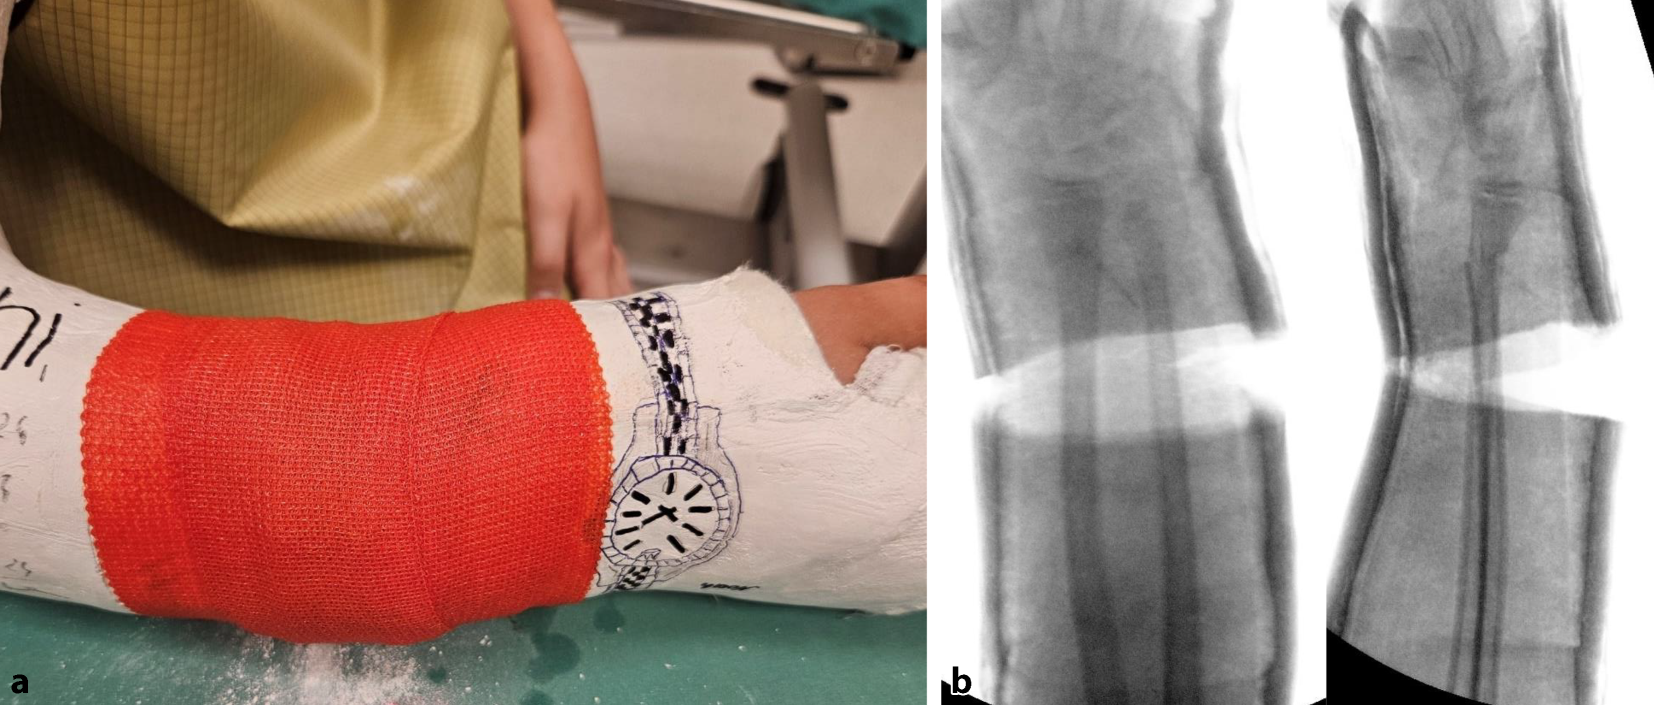

Abb. 8

Stellungskontrolle mittels Bildwandler (achsengerechte Konsolidierung am Unterschenkel als Behandlungsziel). Ausfüllen des gesamten Spaltes mit hölzernen Platzhaltern, die in der Klinik des Autors in verschiedensten Ausfertigungen vorliegen. Zur Vermeidung eines „Fensterödems“ ist darauf zu achten, dass die Keilungsstelle zur Gänze mit den Platzhaltern ausgefüllt ist. Diese müssen in der richtigen Tiefe platziert sein, ein Druck auf den Filz ist zwecks Schonung der Weichteile strickt zu vermeiden (a). Alternativ kann der Spalt im Zentrum mit Holzstücken und am Rand mit entsprechend zugeschnittenen Korkstücken ausgefüllt werden (b). In der Literatur kommen auch vorgefertigte Platzhalter aus Hartplastik zur Anwendung [4]

Abb. 9

Als letzter Schritt wird die Keilungsstelle mit einer zirkulären Kunststoffbinde verschlossen, die im seltenen Fall einer notwendigen Nachkeilung, wobei der Spalt weiter aufgekeilt und ein größerer Platzhalter eingefügt wird, wieder entfernt werden kann (a). Das definitive Keilungsergebnis wird radiologisch dokumentiert (b)